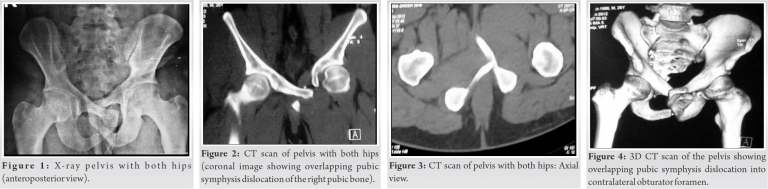

A 26-year-oldman presented to us following a high-velocity road traffic accident. He was unable to walk or pass urine after the injury. Following initial treatment elsewhere, he was referred to our hospital 2 days later for the treatment of the pelvic injury. There was a history of acute urinary retention, blood at the urethral meatus, and failed Foley’s catheterization. On arrival in the ER, the patient was hemodynamically stable with a Glasgow Coma Score of 12/15 and a suprapubic catheter (SPC)insitu. There was extensive ecchymoses over the suprapubic area and Morel-Lavallée lesion over the right proximal thigh and greater trochanteric region. The patient had tenderness on palpation of the right sacroiliac joint and symphysis pubis. His right anterior superior iliac spine was elevated anteriorly and displaced medially, but no apparent limb length discrepancy was noted. He was unable to perform an active straight leg raise on the right side. Both hip joints were non-tender with good rotatory movement. His right hip was observed to be in an attitude of hyperextension, adduction, and internal rotation. Digital rectal examination and focused assessment with sonography in trauma scans were normal. Pelvic compression and distraction tests were not performed because of the pain. Anteroposterior radiograph (Fig. 1) and computed tomography (CT) scan with 3D reconstruction of the pelvis (Fig. 2, 3, 4) showed disruption of the symphysis pubis with herniation of the right pubis into the left obturator foramen. This was associated with the right sacroiliac disruption.